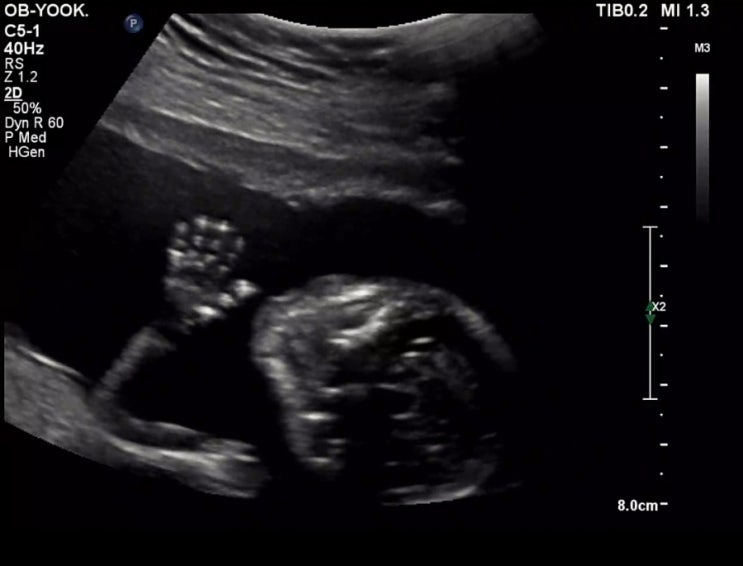

[🤰임신이야기] 둘째 태동느끼는 시기 | 임신 16주 증상 | 전치태반 의심으로부터 해방

임신 16주 초음파 & 증상 둘째 태동 느끼는 시기 전치태반 해방 (태반 위치 올라감) 임신 16주 초음파 ...